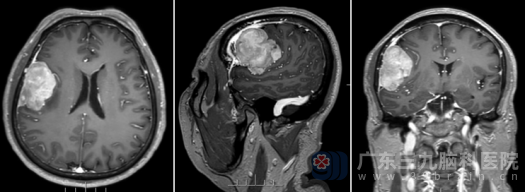

为进一步明确诊断,陈某于2月26日在该院神经外科门诊接受了头颅磁共振(MRI)检查,结果显示右侧额部存在一个约50mm×48mm×30mm的占位性病变。面对这颗悄然生长在颅内的“不速之客”,患者及家属心急如焚,为寻求更专业的治疗,他们慕名来到广东三九脑科医院神经外十科。

入院时,陈某神志清醒,但左侧肢体肌力已下降至4+级(正常为5级)。为更精确地评估病情,神经外十科团队为其安排了详细的术前磁共振检查。结果显示,在右侧额颞顶部颅骨内板下,存在一个范围约53×32×54mm的团块状异常信号影,邻近脑膜也有强化信号,这一切都指向了脑膜瘤的可能性。